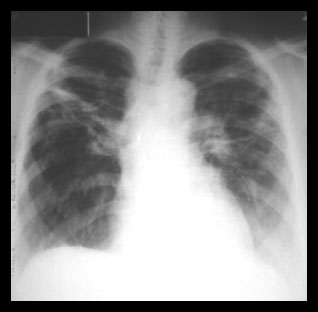

This pattern of widespread interstitial lung disease is a common appearance of sarcoidosis involving the lung parenchyma. Note enlarged hilar lymph nodes. |